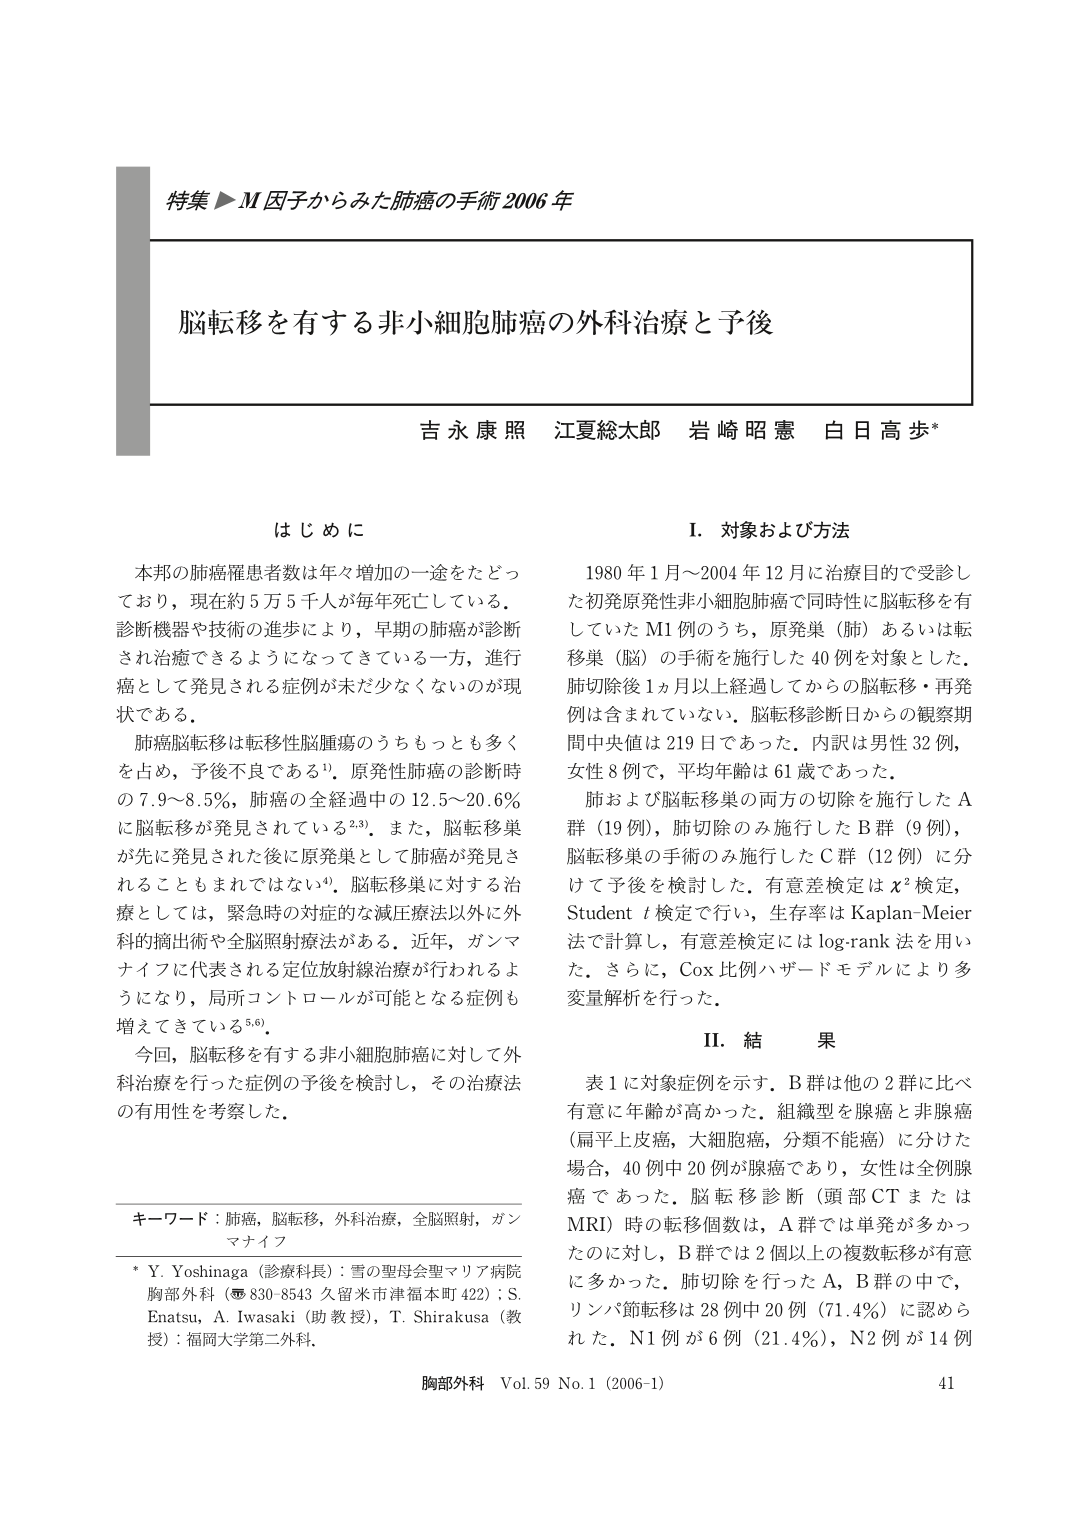

M因子からみた肺癌の手術2006年 脳転移を有する非小細胞肺癌の外科